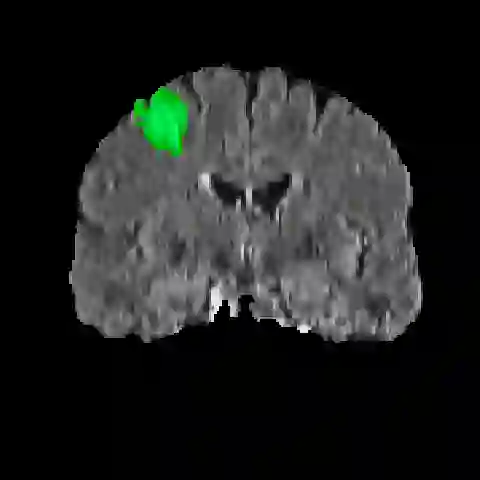

Automatic and accurate tumor segmentation on medical images is in high demand to assist physicians with diagnosis and treatment. However, it is difficult to obtain massive amounts of annotated training data required by the deep-learning models as the manual delineation process is often tedious and expertise required. Although self-supervised learning (SSL) scheme has been widely adopted to address this problem, most SSL methods focus only on global structure information, ignoring the key distinguishing features of tumor regions: local intensity variation and large size distribution. In this paper, we propose Scale-Aware Restoration (SAR), a SSL method for 3D tumor segmentation. Specifically, a novel proxy task, i.e. scale discrimination, is formulated to pre-train the 3D neural network combined with the self-restoration task. Thus, the pre-trained model learns multi-level local representations through multi-scale inputs. Moreover, an adversarial learning module is further introduced to learn modality invariant representations from multiple unlabeled source datasets. We demonstrate the effectiveness of our methods on two downstream tasks: i) Brain tumor segmentation, ii) Pancreas tumor segmentation. Compared with the state-of-the-art 3D SSL methods, our proposed approach can significantly improve the segmentation accuracy. Besides, we analyze its advantages from multiple perspectives such as data efficiency, performance, and convergence speed.